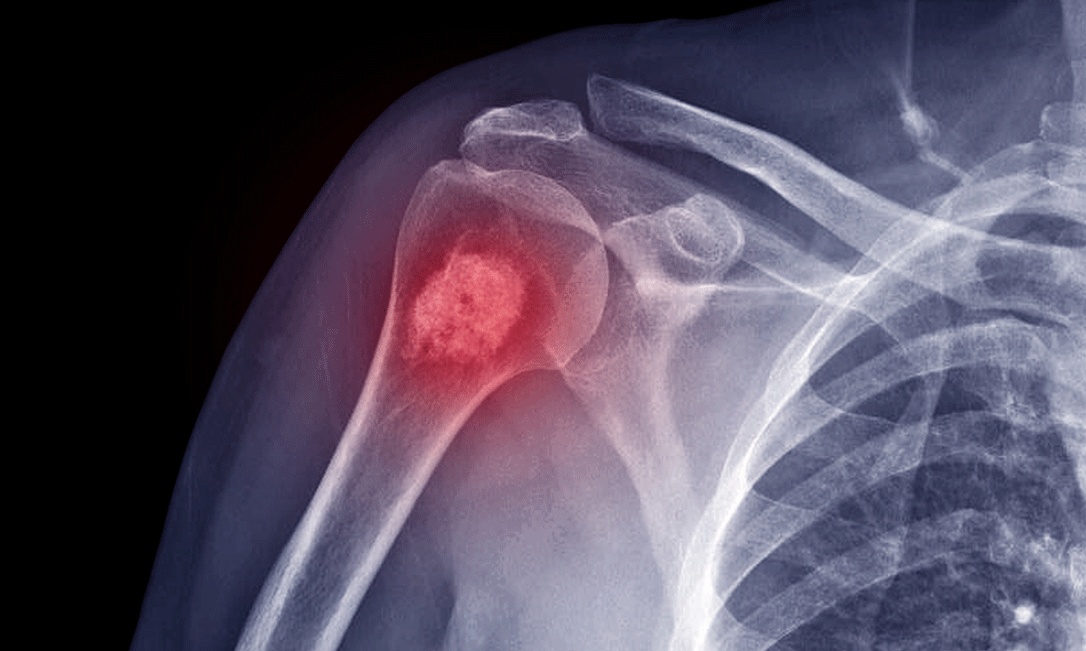

Câncer nos ossos | Foto: Reprodução/Internet

Câncer de ossos, conhecido como sarcoma ósseo, é uma doença agressiva que afeta células e ocorre em qualquer parte do corpo. O principal sintoma é dor óssea crescente e persistente, que pode piorar à noite ou com o uso do osso. Fatores de risco incluem mutações genéticas, exposição à radiação, lesões ósseas e idade (jovens e adultos mais velhos).

Embora seja menos comum do que outras variantes, o câncer de ossos, também conhecido como sarcoma ósseo, é uma patologia de células que começa a crescer sem controle em qualquer parte do corpo. A doença pode ser muito agressiva e exigir tratamentos intensivos, como explica a Sociedade Americana do Câncer.